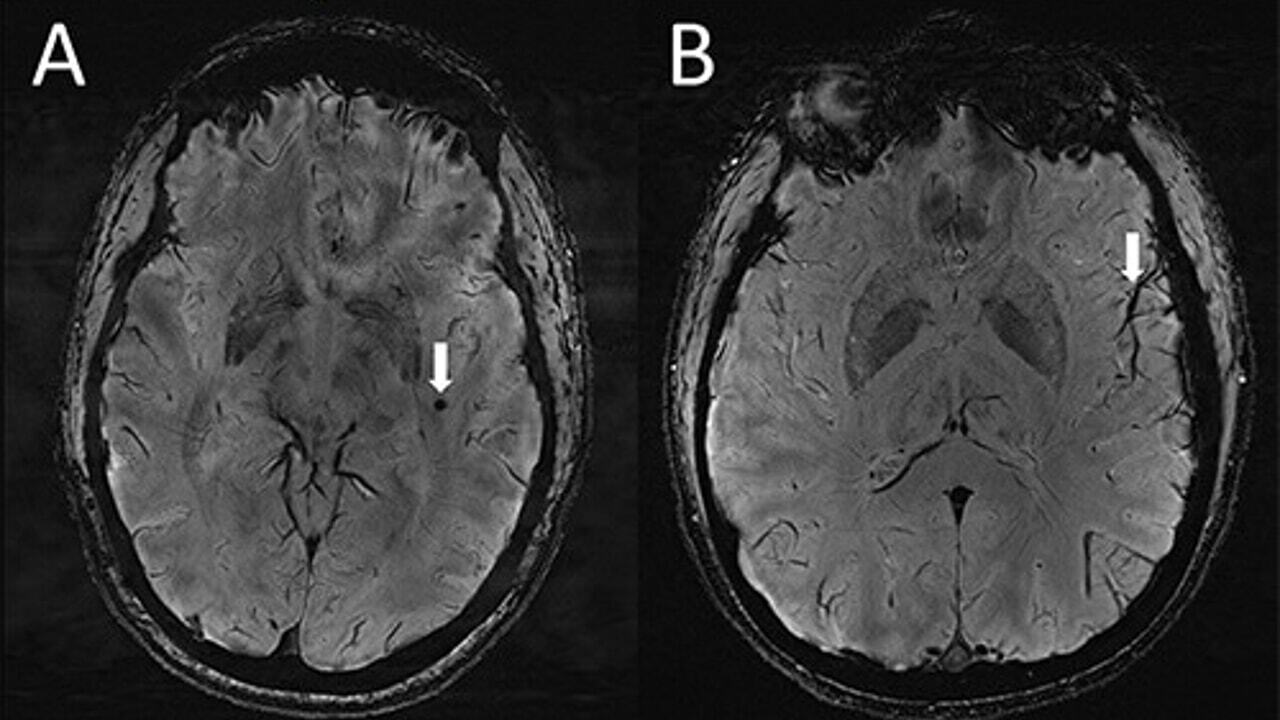

Теперь группа исследователей из Университета Южной Калифорнии в Лос-Анджелесе сделала интригующее открытие, которое может помочь разгадать тайну мигрени. Используя МРТ сверхвысокого разрешения, исследователи обнаружили, что периваскулярные пространства (вокруг кровеносных сосудов в головном мозге) необычно увеличены у страдающих мигренью, как хронической, так и эпизодической. Хотя связь или роль мигрени еще предстоит установить, открытие может послужить отправной точкой для разработки новых методов лечения. Результаты исследования были представлены на 108-й Научной ассамблее и ежегодном собрании Радиологического общества Северной Америки.

Для изучения связи между мигренью и изменениями периваскулярного пространства исследователи набрали 20 пациентов в возрасте от 25 до 60 лет с мигренью: 10 с хронической мигренью без ауры (отсутствие симптомов, предшествующих головной боли) и 10 с эпизодической мигренью. Кроме того, в качестве контрольной группы были включены 5 здоровых пациентов, не страдающих мигренью. Исключались пациенты с когнитивными нарушениями, клаустрофобией, опухолью головного мозга или ранее перенесшие операции на головном мозге. Чтобы изучить структурные микрососудистые изменения при двух типах мигрени, исследователи сканировали мозг пациентов с помощью нового типа МРТ: МРТ 7 тесла. «Насколько нам известно, — сказал Сюй, —

«Поскольку 7 Т МРТ способна генерировать изображения головного мозга с гораздо более высоким разрешением и лучшим качеством, чем другие типы МРТ, ее можно использовать для демонстрации гораздо меньших изменений, происходящих в тканях головного мозга после мигрени».

Сканирование выявило значительные изменения периваскулярных пространств в centrum semiovale (центральная область белого вещества головного мозга) у людей с хронической мигренью и эпизодической мигренью без ауры. В частности, эти пространства были больше, чем в контрольной группе. «Об этих изменениях, — подчеркнул Сюй, — никогда раньше не сообщалось». Исследователи предполагают, что значительные различия в периваскулярных пространствах у пациентов с мигренью по сравнению со здоровыми субъектами могут свидетельствовать о нарушении лимфатических узлов в головном мозге. «Глимфатическая система, — объяснил Сюй, — это система удаления отходов, которая использует периваскулярные каналы, чтобы помочь вывести растворимые белки и метаболиты из центральной нервной системы. Однако,

Исследователи также обнаружили, что увеличение периваскулярного пространства в полуовальном центре связано с повышенной гиперинтенсивностью белого вещества у пациентов с мигренью. Эти гиперинтенсивные образования проявляются в виде белых пятен или ярких поражений на МРТ-сканах, и, хотя они не являются чем-то необычным, в настоящее время они все еще плохо изучены. Известно, что у многих людей они начинают проявляться после достижения шестидесятилетнего возраста и что те же самые изменения, вызванные этими поражениями, имеют тенденцию усиливаться с возрастом.

Изучая снимки, исследователи отметили, что частота этих поражений была одинаковой между пациентами с мигренью и контрольной группой, однако их тяжесть у пациентов с мигренью была выше. Это предполагает, по мнению авторов исследования, что расширение периваскулярных пространств может привести к дальнейшему развитию большего количества поражений белого вещества.